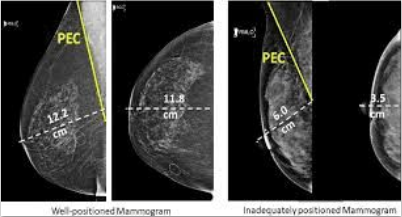

Automatização da detecção de câncer de mama com análise de mamografias e dados clínicos.

Desenvolvimento de um algoritmo capaz de classificar a qualidade do posicionamento de exames de mamografia.